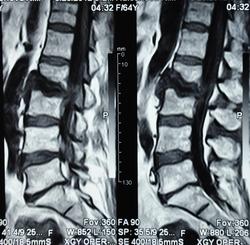

Можно гадать, но без клиники и анамнеща никак. Исходя из картинок больше на пиогенный вроде. Хотя, и тубер может выглядеть так же.

Наверное, правильнее это можно назвать спондилодисцитом ( не туберкулезной этиологии)

Как-то  ( боюсь повториться, но что делать!) наш преподаватель по рентгенологии в Хабаровске говаривал:"Если больного принесли на носилках из-за невозможности движений, то это  пиогенныый ( гематогенный) спондилит, если пришел сам, на своих ногах, то туберкулезный."Еще нас учили, что размеры деструкции в одном позвонке при гематогенном поражении больше, чем в следующем позвонке, при туберкулезном-2 и более позвонка поражены одинаково;реактивный склероз  чаще встечается при гнойных процессах, при туберкулезе-как правило, не бывает; процесс при туберкулезе протекает медленнее,при гематогенном-может молниеносно ;наличие туберкулеза  других органов и систем ( не обязательно).

Мне видится здесь последствия зверского дисцита.  Предположу, ситуация не острая - данных за отек соответсвующих позвонков нет, хотя для убедительности нужен FatSat.  Из этого делаем вывод- на первое место исход воспаления, с формированием кистозных изменений, на второе - быть может нечто постравматическое с последующим, опять же, дисцитом.

При пункция патологического участка позвоночника - Лимфома позвоночника. Передан онкологам на лечение.

Уважаемый Николас, диагностировать лимфому по представленным сканам-высший пилотаж.Аксиалы, короналы напрочь отсутствуют-как можно обнаружить паравертебральный мягкотканный компонент ( если он имеет место быть, конечно)????.А вот явные признаки спондилодисцита имеются.

По мне так спондилодисцит. Характерный жидкостной сигнал в диске, деструкция смежных позвонков. А уж какой этиологии, это пусть клиницисты решают.